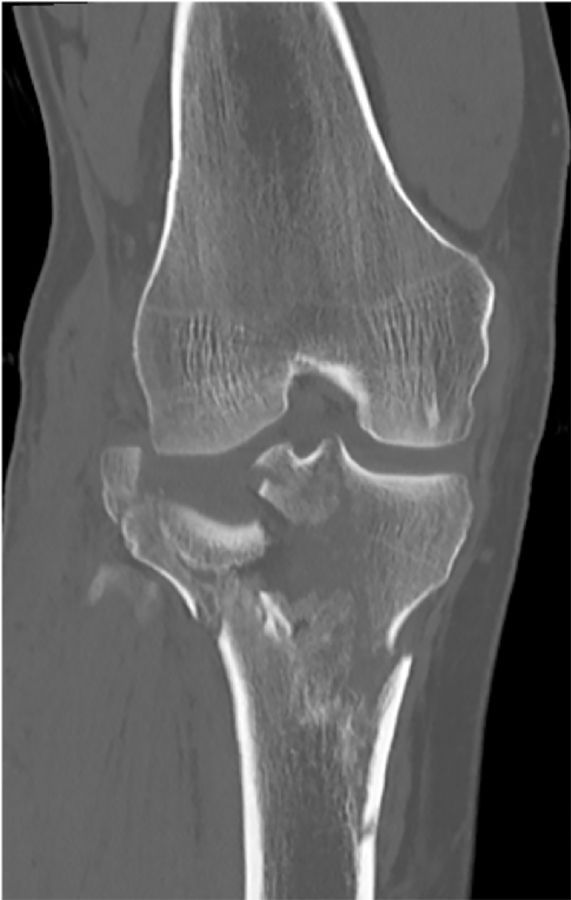

Exposure of the knee can be quite difficult especially if the stiffness is the result of bony impingement. I remember a few patients with intraarticular distal femur fractures that had healed in such a malposition that the resulting step off blocked the flexion of the knee (Figure 9a, b, c).

Dealing with this situation in a knee with less than 45 degrees of flexion requires a very careful step by step exposure. Usually I start by performing a medial capsular release to be able to externally rotate the tibia as far as possible. Once this allows flexion of the knee to 40 to 60 degrees distal resection of the femur can be attempted. Further flexion is achieved with a free hand cut of the proximal tibia to disengage the bony impingement. Despite opening up the extension gap it can be difficult to flex the knee and expose the tibia without a femoral peel and release of the MCL (Figure 10) to allow for separation of the femur from the tibia [6].